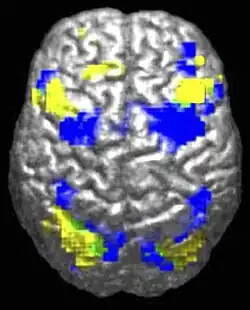

The beginnings of empathy lie in the brain. When a person empathises with another person, their brain triggers neurons that match the neurons in the brain of the person in distress. Or quite simply, just by perceiving an emotion in someone the neuron mechanisms that are responsible for that emotion in our brains are switched on. This phenomenon was first discovered from studies on rhesus monkeys, in which a class of neurons called mirror neurons were found in the ventral premotor and posterior parietal cortices in the brain. (Rizzolatti, Fogassi & Gallese, 2001 cited in Decety & Meyer, 2008). The evidence for mirror neurons in humans is a little less solid, however studies using functional magnetic resonance imaging (fMRI) have found similar results involving pain - when a person perceives someone in pain, the neural circuits for pain in the observer are activated, as if they too are experiencing pain (Decety & Meyer, 2008; Mikulincer & Shaver, 2010).

Empathy theorist Jean Decety also proposes that the experience of empathy likely involves other parts of the brain, such as the frontopariental and prefrontal circuits, as the person empathising must be able to differentiate himself or herself from the person in distress. In addition, executive functions instantiated in the prefrontal cortex may play a part, as this part of the brain helps to regulate emotions and yield mental flexibility (Decety & Meyer, 2008).